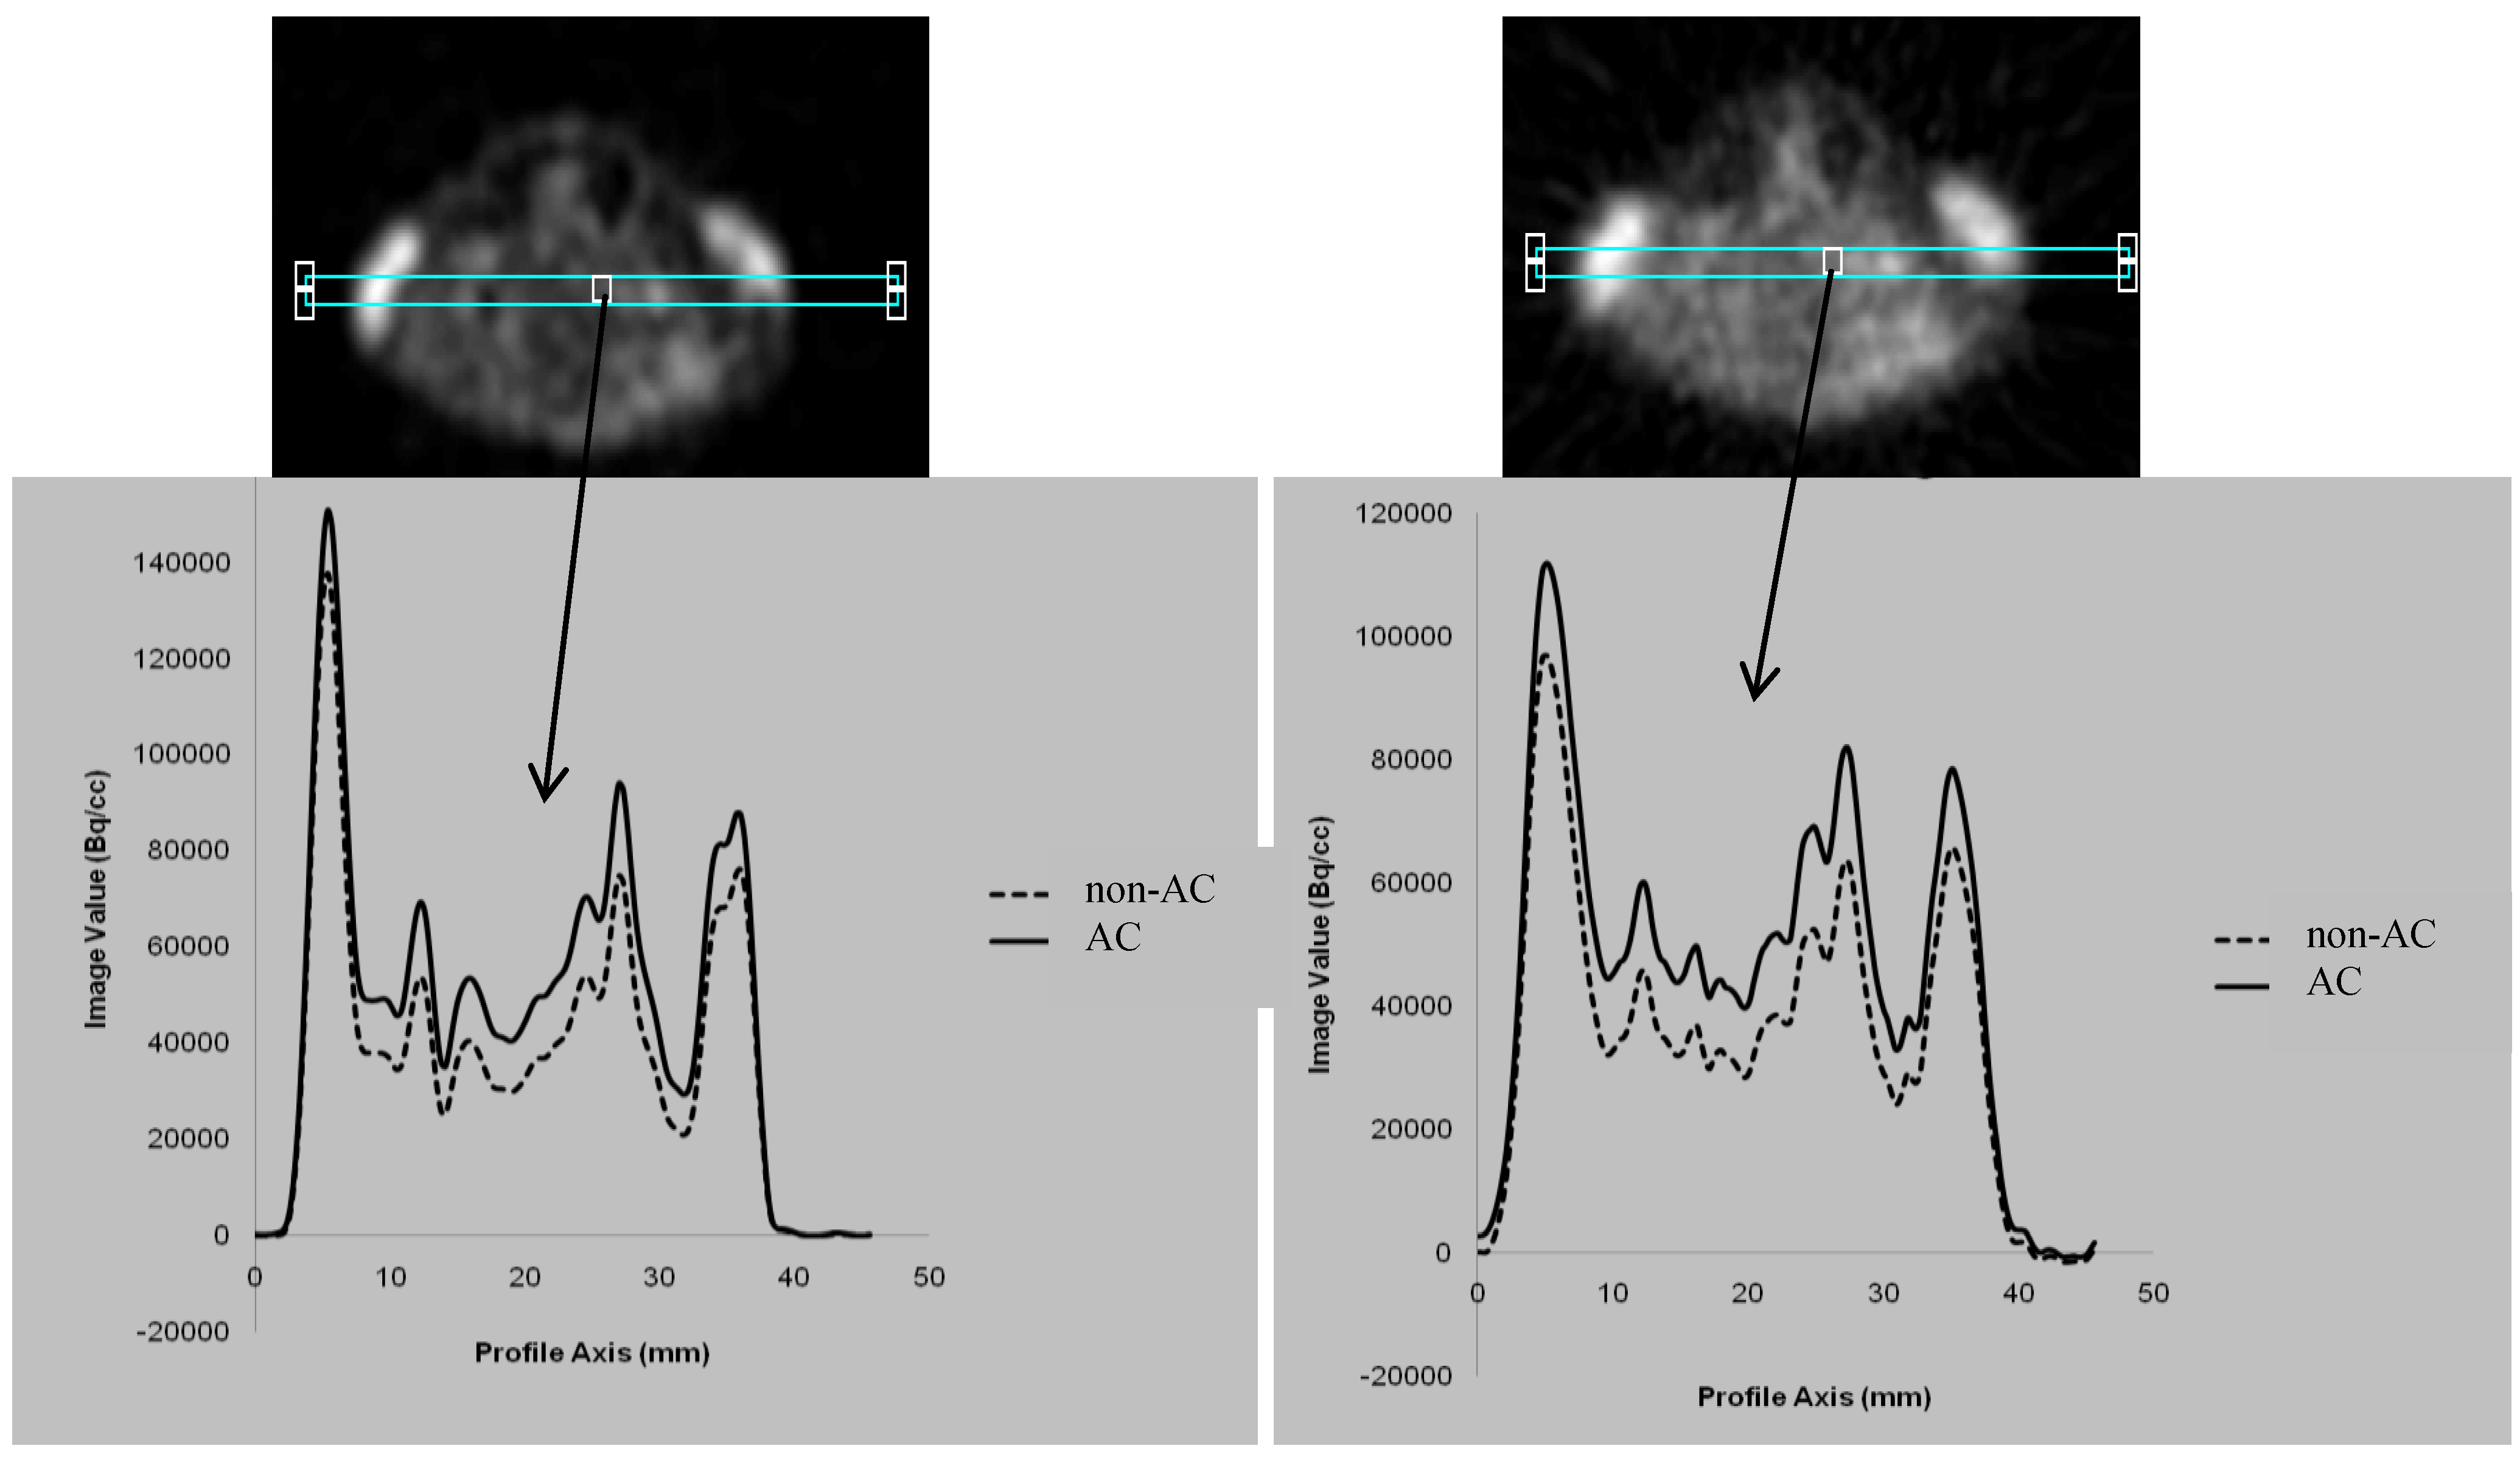

3.1. Comparison between the AC and non-AC PET Data